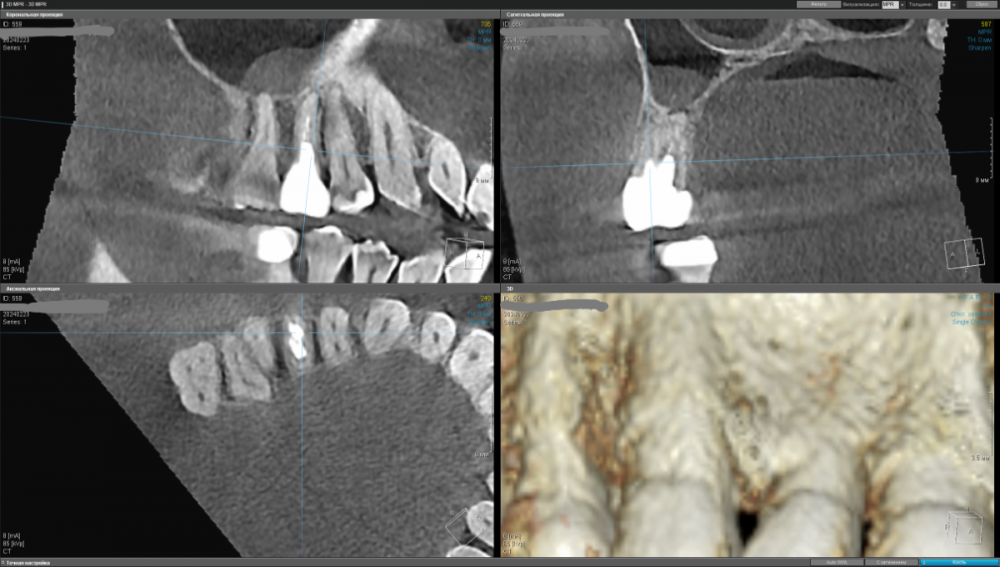

kamacho Опубликовано 24 февраля, 2024 Автор Поделиться Опубликовано 24 февраля, 2024 Попробую привлечь ваше внимание дополнительными снимками. Вопросы которые я себе задаю когда смотрю на КТ: 1) Между 14 и 15 зубом, это убыль фуркации или артефакт при съемке кт ? 2) В районе 37 ого зуба это артефакт или кариес ? Я пытаюсь санировать ротовую полость уже наверное лет пять, и никогда не удается решить проблему. Прошел множество клинник (наверное штук 5-6, включая 1 зарубежную). Но после попыток лечения, возникает одна и таже проблема, как только начинаю добавлять углеводы(не сладости) в рацион, какой-то очаг инфекции дает о себе знать. Буду очень признателен если поможете советом или догадкой. Ссылка на комментарий

kamacho Опубликовано 24 февраля, 2024 Автор Поделиться Опубликовано 24 февраля, 2024 (изменено) Так же приложу документ-опись риентгенолога по всем зубками с изображениями. снимок был сделан в 22 году. Наврятли кто-либо захочет перечитывать такое количество информации ради развлечения. Но для истории добавлю. Изменено 24 февраля, 2024 пользователем kamacho Ссылка на комментарий

Carioznik Опубликовано 25 февраля, 2024 Поделиться Опубликовано 25 февраля, 2024 15.02.2024 в 18:43, kamacho сказал: есть ли показания для лечения этого зубика? По идее есть, но нужно разбираться 15.02.2024 в 18:43, kamacho сказал: Могут ли не до конца пролеченные корни вызывать такую симптоматику ? Нет 17 часов назад, kamacho сказал: Между 14 и 15 зубом, это убыль фуркации Нет. Похоже, что на 14 есть кариес. Возможно это и причина кровоточивости и запаха. Но нужно смотреть настоящую КТ , а не скрины. 18 часов назад, kamacho сказал: районе 37 ого зуба это артефакт или кариес ? Больше на артефакт похоже, но это не точно: нужно смотреть настоящую КТ , а не скрины 1 Ссылка на комментарий